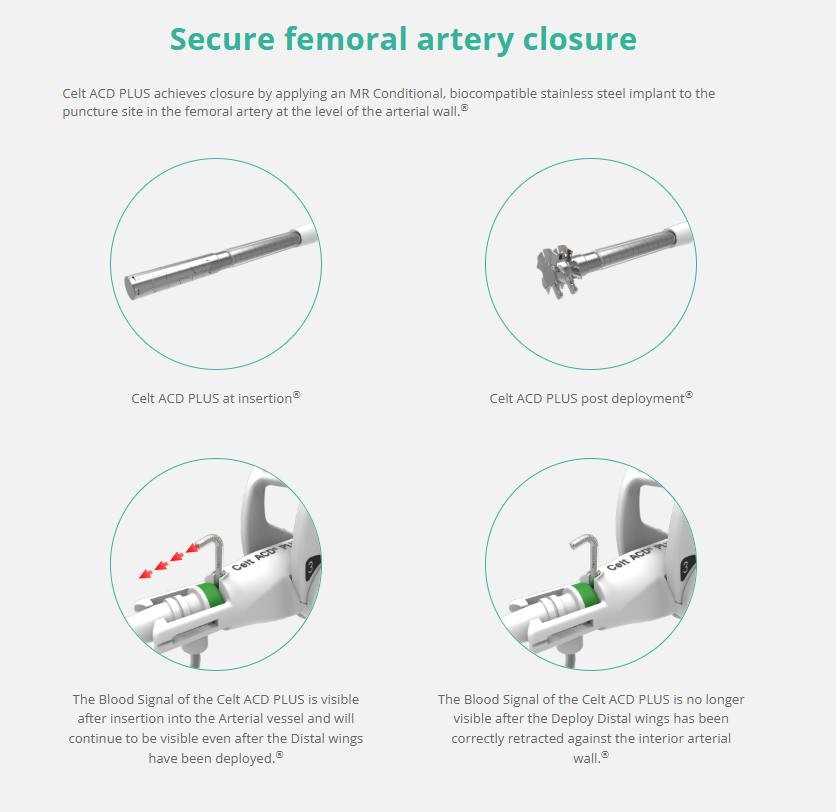

Vasorum Celt ACD PLUS

项目类型

器械质押区

起投金额

6500USDT

每日释放:0.9

释放周期:30 天

已购: 15230

剩余: 0